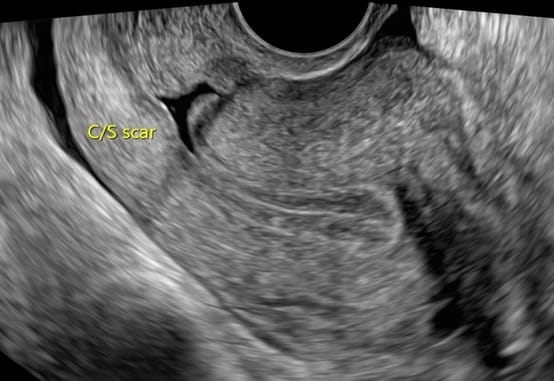

子宮下段缺損積血的超音波畫面。 圖:陳碧華醫師/提供

由於該病患同時伴隨剖腹產手術後常見併發症的子宮下段缺損積血,陳碧華透過赫拉冷刀雷射治療子宮下段缺損,並利用系統子宮鏡光源引導,於子宮內頸口凹陷處置入膠原蛋白基質粉輔助患部修復。她強調,赫拉刀系統的應用範圍極廣,不只適合治療子宮息肉與肌瘤,更能廣泛應用於取出避孕器、停經後出血檢測及早期內膜癌診斷,對於未完成生育或停經後更年期不正常出血的患者,提供精準、溫和的治療選擇。

子宮健康是許多女性生活品質的重要指標,不正常出血或長期貧血往往隱藏著子宮求救的訊號。一名曾有輸卵管子宮外孕及剖腹產史的43歲女性,長期受異常月經與陰道出血困擾,經超音波檢查後發現患有「子宮肌腺瘤」及「子宮下段缺損積血」,抽血檢查也發現已有輕微貧血。經雙和醫院婦產科醫師陳碧華規劃,安排點滴麻醉進行赫拉刀子宮鏡檢查,併用鈥雷射汽化消融子宮下段纖維化肌腺瘤,協助解決病灶,最後利用膠原蛋白基質粉的硬帽部分放在子宮內頸口凹陷傷口處輔助癒合,患者回饋術後子宮恢復良好,成功找回健康生活。